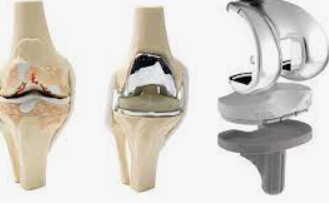

인공 관절 수술은 관절의 퇴행성 변화, 외상, 또는 다른 질환으로 인해 손상된 관절을 인공적인 재료로 만든 관절로 교체하는 의료 절차입니다. 이 수술은 주로 무릎, 고관절, 어깨 관절 등에 적용되며, 환자의 삶의 질을 향상시키고 통증을 감소시키는 데 목적이 있습니다.

인공 관절 수술의 종류는 크게 두 가지로 나뉩니다: 전치환술과 부분치환술입니다. 전치환술은 손상된 관절 전체를 인공 관절로 교체하는 방법이며, 부분치환술은 손상된 관절의 일부만을 교체하는 방법입니다. 환자의 상태와 필요에 따라 적절한 수술 방법이 선택됩니다.

전치환술은 관절의 변형이 심하거나 손상 부위가 넓은 경우에 주로 사용됩니다. 이 수술은 관절의 안쪽과 바깥쪽 모두를 인공 관절로 바꿔줌으로써, 통증을 줄이고 관절의 기능을 회복시키는 데 도움을 줍니다.

반면, 부분치환술은 관절의 손상이 비교적 제한적인 경우에 적합합니다. 이 수술은 절개 부위가 작고 회복이 빠르며, 무릎 운동 범위의 제한이 적다는 장점이 있습니다. 특히, 연골 내측만 손상된 경우나 십자인대 기능이 정상인 경우에 시행됩니다.